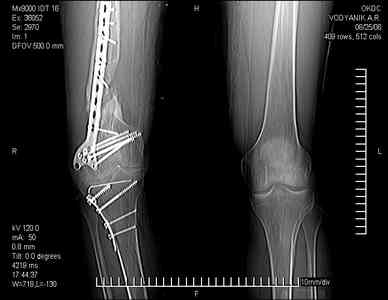

Тугой ложный сустав правого бедра в сочетании неправильно сросшимся переломом большеберцовой кости

В 2002 v внутрисуставной оскольчатый перелом проксимального метаэпифиза правой большеберцовой кости; в 2005 v внутрисуставной оскольчатый перелом дистального метаэпифиза правой бедренной кости.

В обоих случаях в разных лечебных учреждениях проводилось оперативное лечение переломов. При осмотре в отделении на основании результатов клинического осмотра и данных визуальных методов обследования поставлен диагноз: тугой ложный сустав дистальной трети правой бедренной кости, состояние после накостного остеосинтеза перелома типа 33-В2.2 ; несросшийся перелом надколенника; неправильно сросшийся перелом латерального мыщелка правой большеберцовой кости, состояние после металлоостеосинтеза перелома 41-В2.2; сочетанная осевая деформация правой ноги: варусная деформация правого бедра, вальгусная деформация правой голени; посттравматический артроз коленного сустава 4 ст по Kellgren-Lowrence; выраженное нарушение функции ходьбы и опоры.

Внешний вид ноги больного, данные рентгенографического обследования и избирательно выделенные компьютерные томограммы приведены в приложении. В именах КТ использовано кодирование уровня по АО, т.е. _41, например, означает проксимальную треть голени. В отделении намечен v очень предварительно v следующий план лечения: